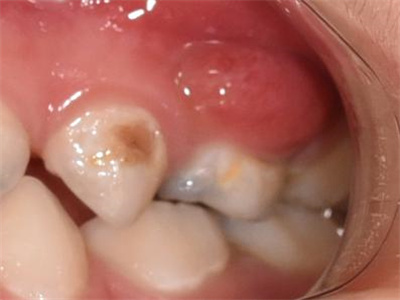

牙龈炎是发生于牙龈组织的炎症,患者可出现牙龈出血伴肿胀、发红、正常形态改变和偶尔不适等症状。本病主要由口腔卫生状况差导致,包括口腔不洁、牙菌斑等,诊断依据临床检查,治疗包括专业牙齿清洁和加强家庭口腔卫生。

牙龈炎常见的病因是口腔卫生差,不良的口腔卫生使牙菌斑沉积于牙齿与牙龈之间,造成龈沟加深,另外牙结石、不良修复体等也可造成牙龈炎的发生。